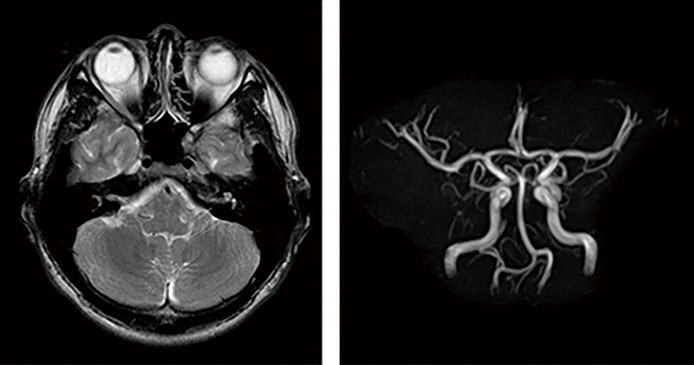

脳ドックでは、まずMRIによる脳の検査が基本となります。MRIでは脳の構造を詳しく見ることができ、同時にMRAという検査で脳や頸の血管も評価します。これらの検査を組み合わせることで、脳そのものと、それを支える血管の状態を同時に確認することができます。特に中高年以降は、脳卒中や脳腫瘍のリスクが高まるため、脳ドックの受診が重要です。

当センターの脳ドックでは、MRI(左画像)に加えてMRA(右画像)も取り入れています。MRIが得意とする脳の小さな梗塞や腫瘍のほか、くも膜下出血の原因となる脳動脈瘤や脳動脈奇形を調べることが可能となり、脳血管疾患の早期発見に強みを発揮します。